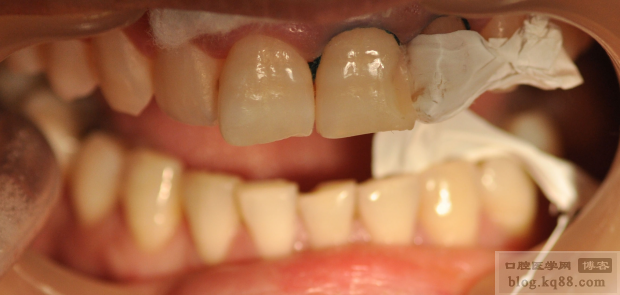

外形恢復(fù)后,制作硅膠導板

硅膠導板完成后,酸蝕牙齒

在硅膠導板上制作背板

背板完成